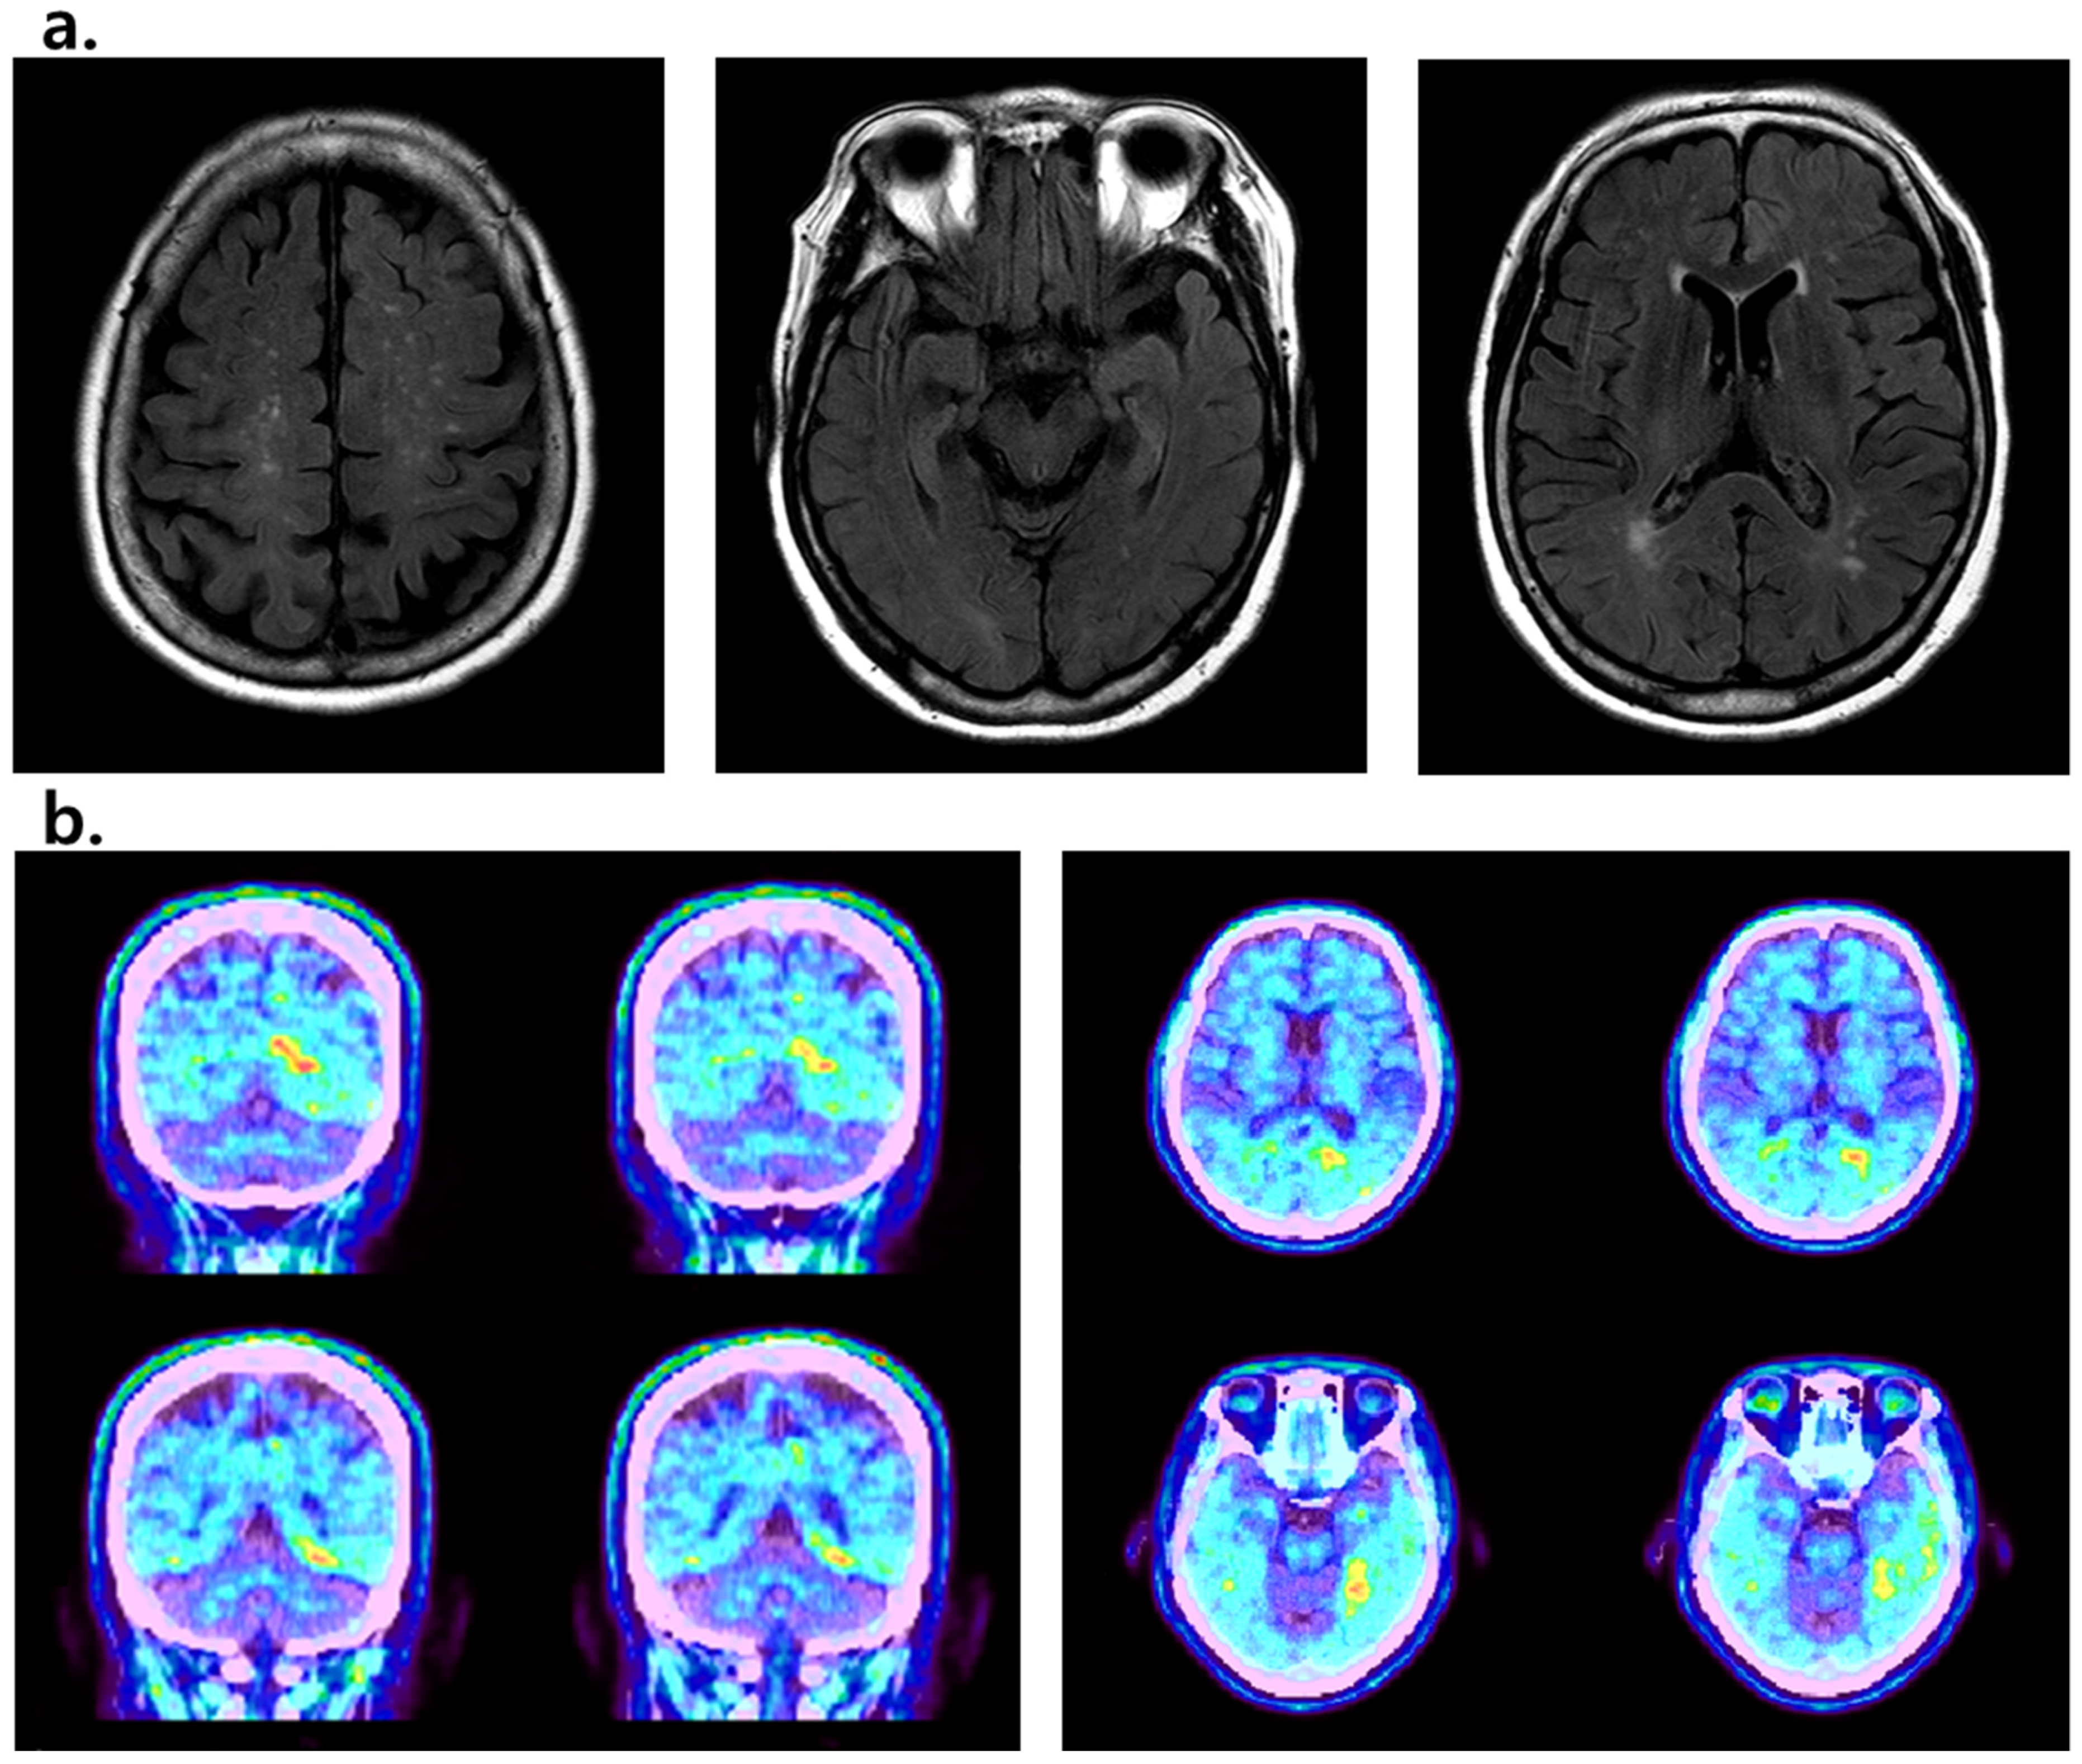

2. Case Presentation